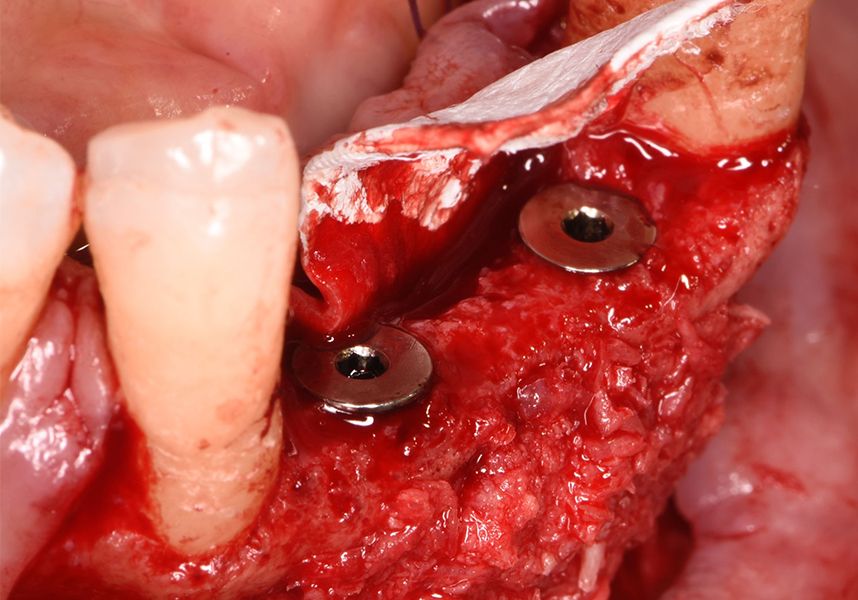

The patient was anesthetized and a flap was made from the distal area of tooth 43 up to 36. Then two Avinent Biomimetic Ocean IC implants of 3.5x10 were inserted in positions 32 and 42.

Respecting the three-dimensionally correct position of the implant led to bone fenestration, leaving the apical part of the apex of the implant exposed almost to the mid-point of its length at 42 and a third in 32.

To treat the defect, bone regeneration was carried out simultaneous to the surgical process, with an autologous bone graft from the patient. In the internal part of the graft we used autologous cortical bone obtained by scraping (Safescraper) and from the biological drilling, at low revolutions and without irrigation, from the other implant beds. In the external layer of the regeneration we used a xenograft (Genoss, Osteogenos) and this was covered with a reabsorbable collagen barrier membrane (Evolution STD, Osteogenos).